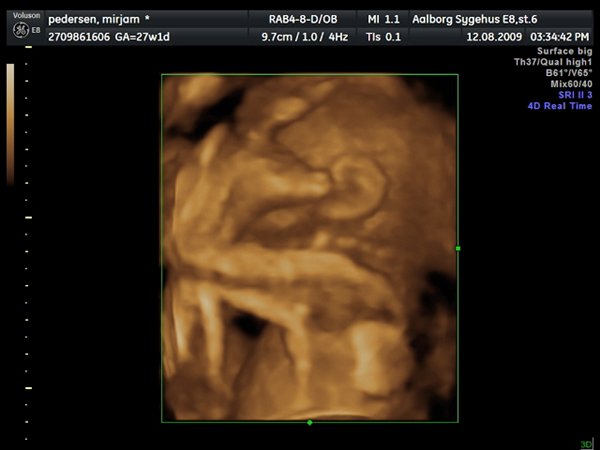

Så var jeg til 3D scanning, og det er en lille PRINSESSE

Hun var bestemt ikke samarbejds villig, vi skulle ihvertfald ikke bestemme hvordan hun sku ligge, så hun lå med hænderne oppe foran hovedet og somme tider med benene oppe foran os.. Så jeg fik rabat kom af med 800kr og han scannede mig ca 50 min. Han sagde hun vejede 990 gram

Vedhæftede fotos (klik for at se i fuld størrelse)